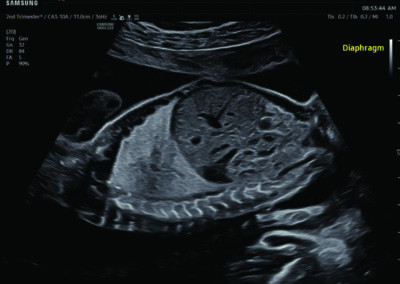

Comprehensive, advanced and expert MFM care for high-risk pregnancies

- Fetal anomalies

- Intrauterine growth restriction